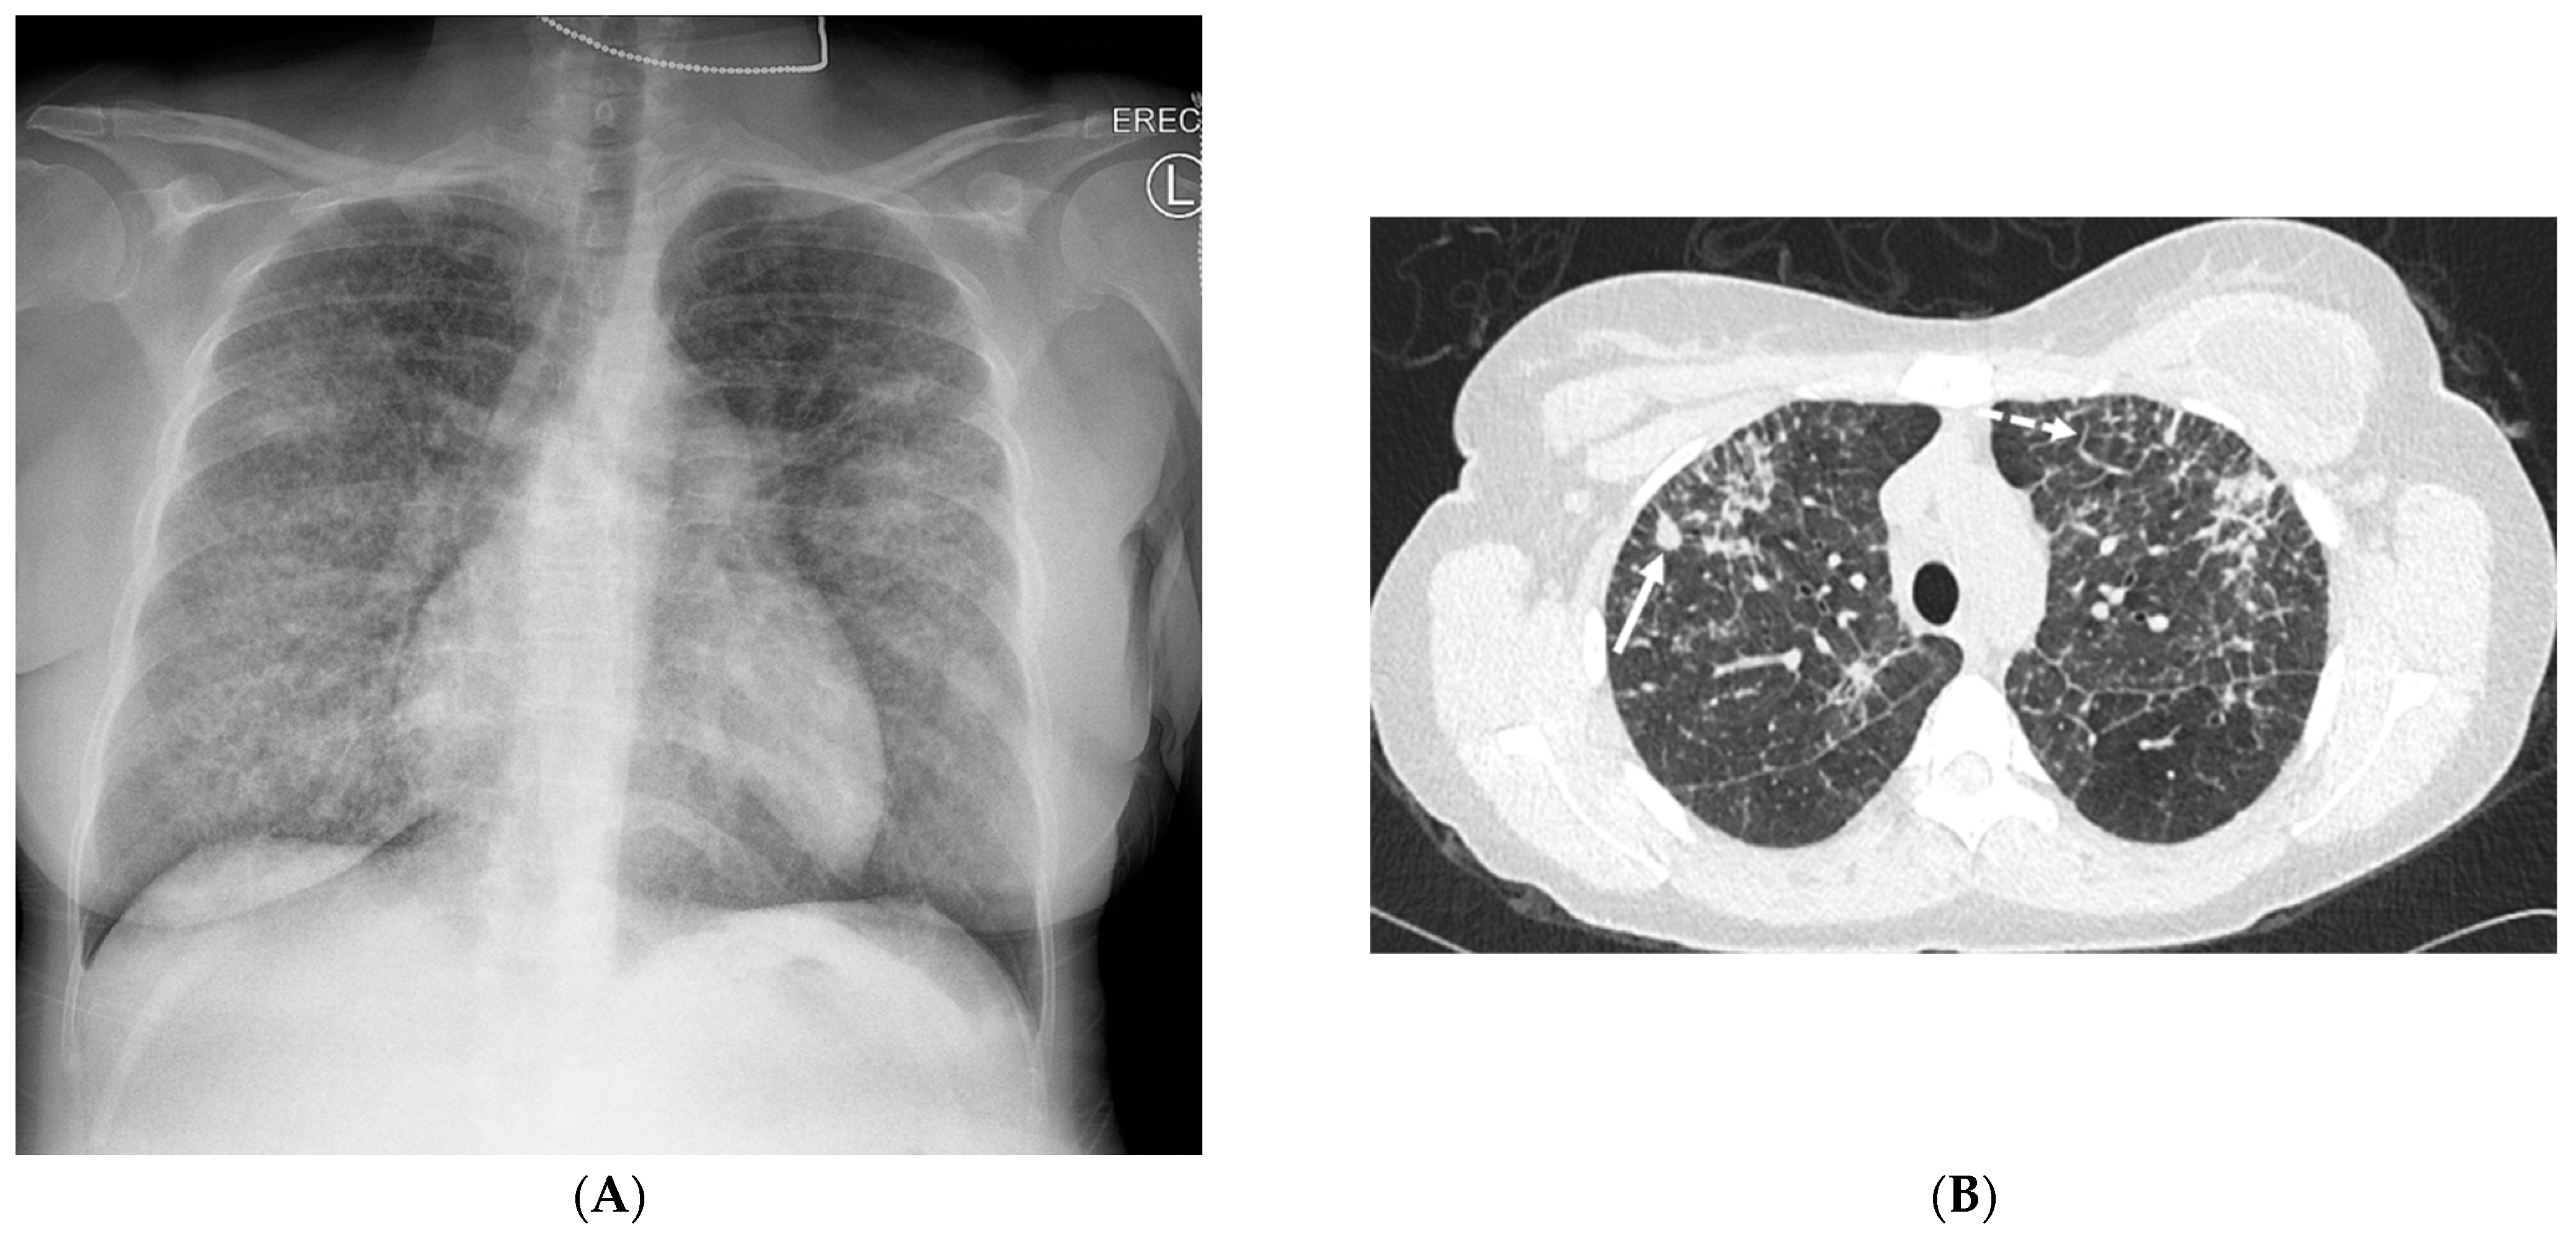

4.6. Silicone Embolization

4.7. Pulmonary Vein Stenosis (PVS)